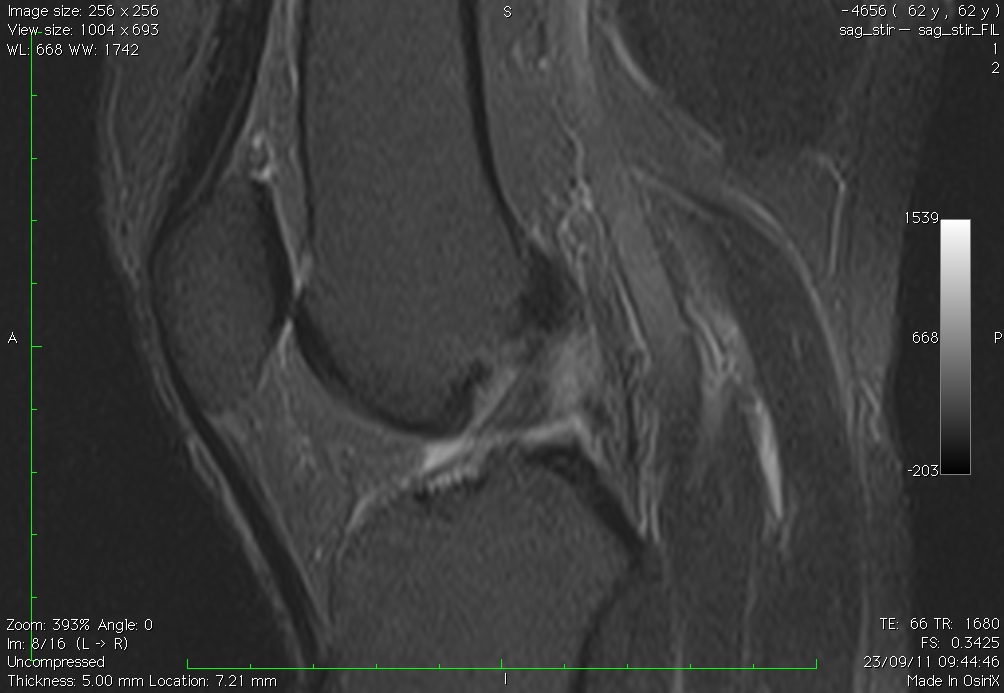

Figura 9. Paciente com rotura completa do LCA, com exposição parcial do corno posterior

do menisco lateral na seqüência com stress femorotibial (imagem à esquerda) em

comparação com a seqüência sem stress (imagem à direita). Este paciente apresenta sinais

de gaveta e exposição meniscal positivas simultaneamente.